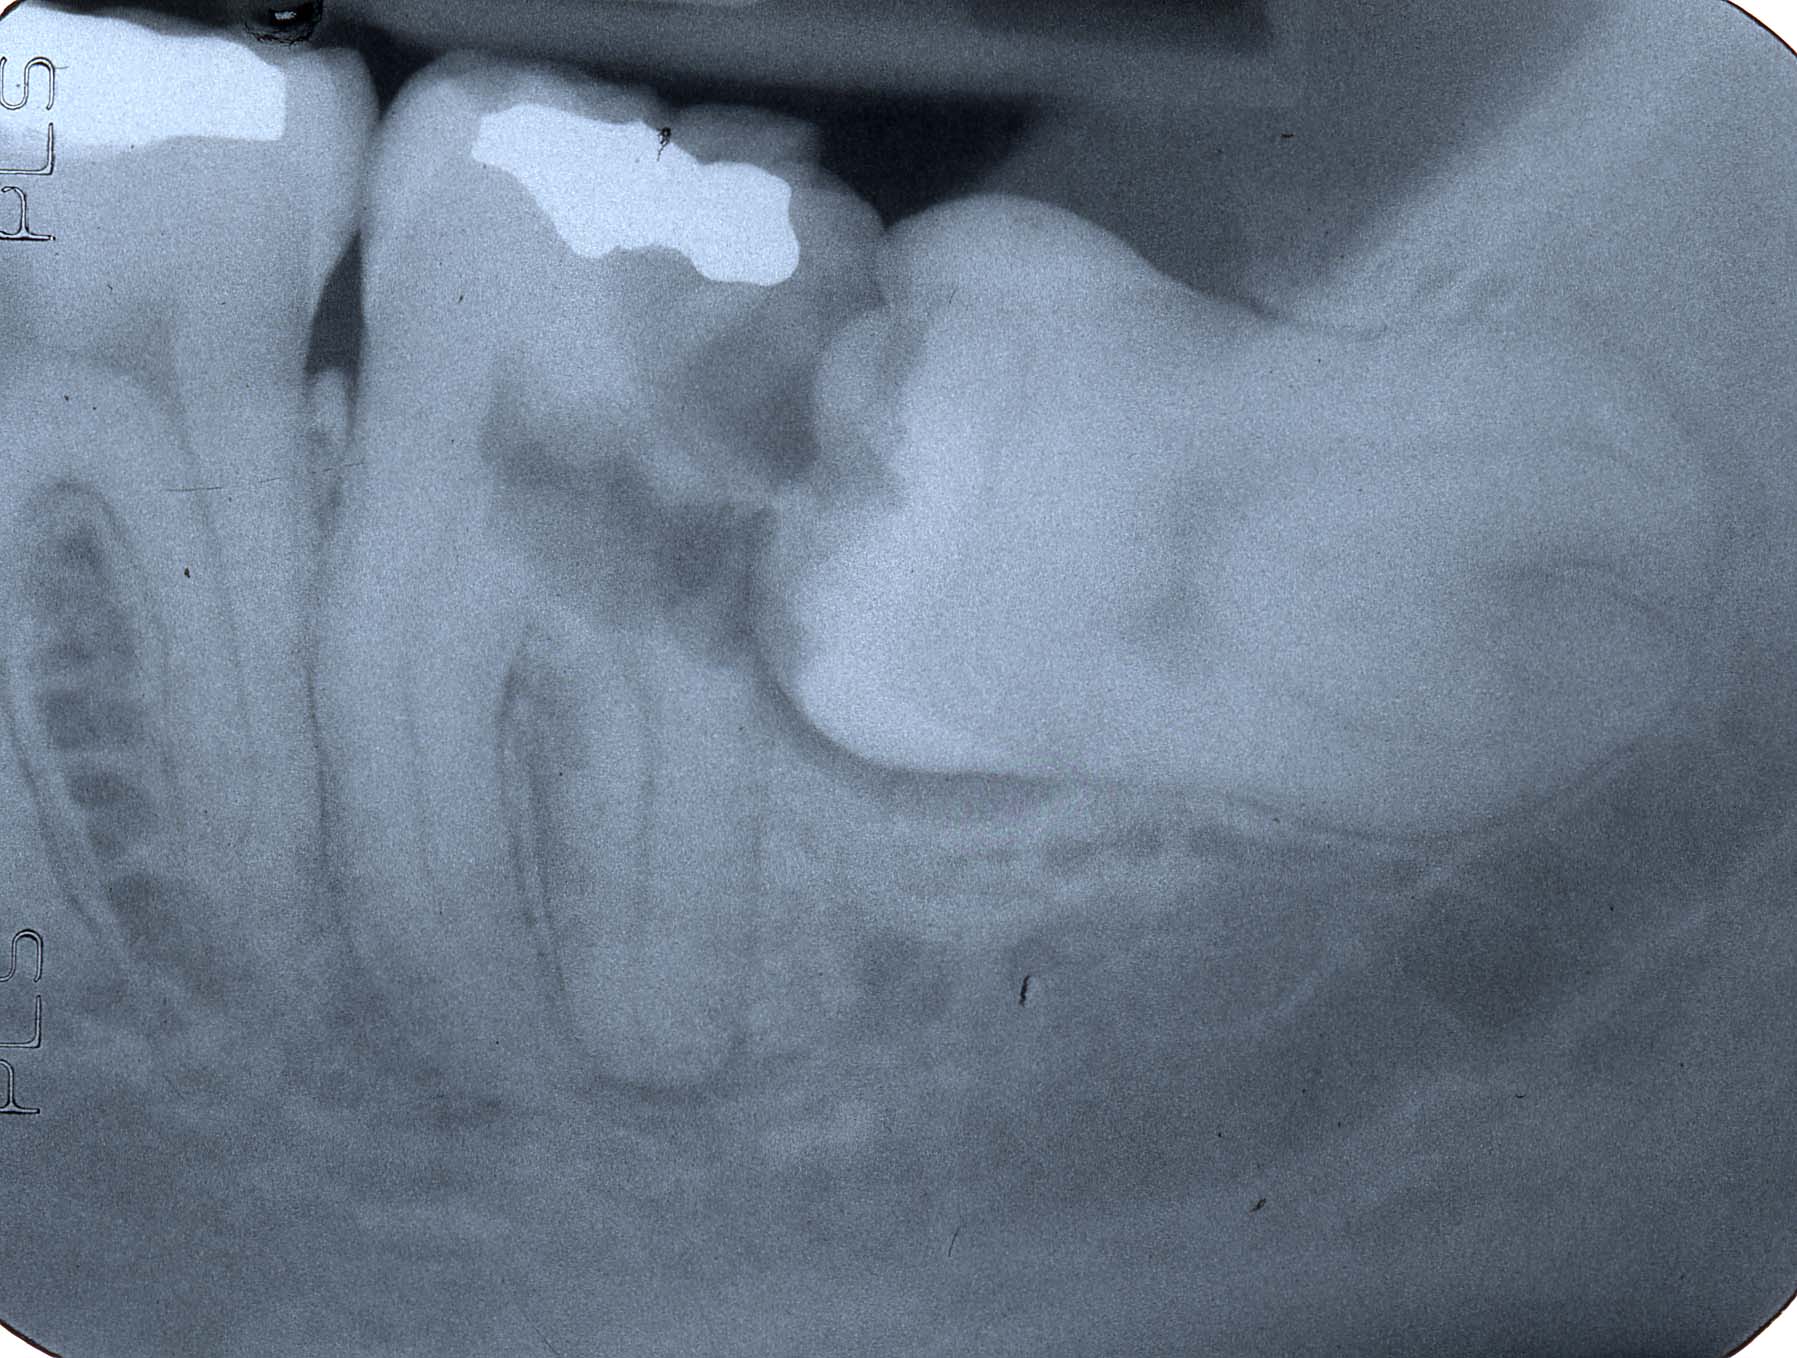

Проблемы при проведении рентгена

В ряде случаев рентген зубов (как часто можно делать его в случае неудачного первого снимка, расскажет лечащий врач) не получается провести должным образом из-за потери организмом пациента контрастности. Это может произойти по нескольким причинам.

На отдельной части челюсти возникла гранулема, абсцесс или киста

Абсцессы, кисты, гранулёмы могут сильно затемнить снимок, сделав невозможными его точное описание и постановку диагноза.

Неправильно проведенное пломбирование каналов

Неверное использование пломбировочного материала или пломбировка каналов после удаления нервов приводят к засвечиванию снимка. Соответственно, разглядеть на нём что-либо не представляется возможным.

Первый этап возникновения цементомы

Снимки зубов на визиографе не получатся в случаях, когда зубы поражены цементомой. Статистика говорит, что такому заболеванию подвержены в основном женщины. В 2% случаев апикальных патологий именно цементома является последствием. На 1-х стадиях болезнь можно увидеть на снимке. Потом же (примерно через полгода) она полностью утрачивает контрастность.

Прицельный

С помощью прицельного снимка удаётся разглядеть конкретный поражённый зуб или несколько. При этом на такой снимок не могут попасть более 4-х зубов.